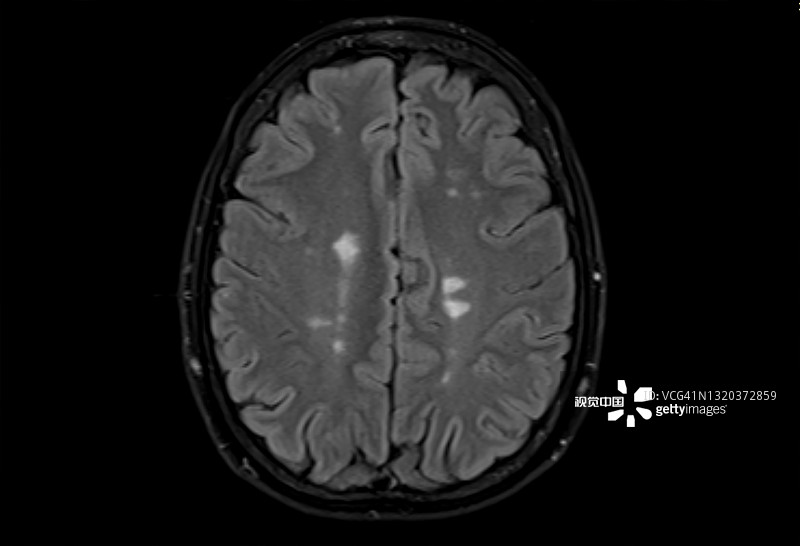

多發(fā)性腦硬化癥的磁共振成像,軸位Flair視圖

多發(fā)性硬化癥 (MS)MS是一種中樞神經(jīng)系統(tǒng) (CNS) 的慢性自身免疫和炎癥性疾病。MS與免疫系統(tǒng)介導(dǎo)的自身反應(yīng)性T細(xì)胞和B細(xì)胞對(duì)神經(jīng)元髓鞘的攻擊有關(guān),導(dǎo)致脫髓鞘并最終導(dǎo)致神經(jīng)元丟失。由于中樞神經(jīng)系統(tǒng)中神經(jīng)變性和斑塊的形成,MS患者會(huì)根據(jù)斑塊的位置經(jīng)歷特定的神經(jīng)功能障礙。例如,視神經(jīng)中的斑塊會(huì)導(dǎo)致視力喪失。